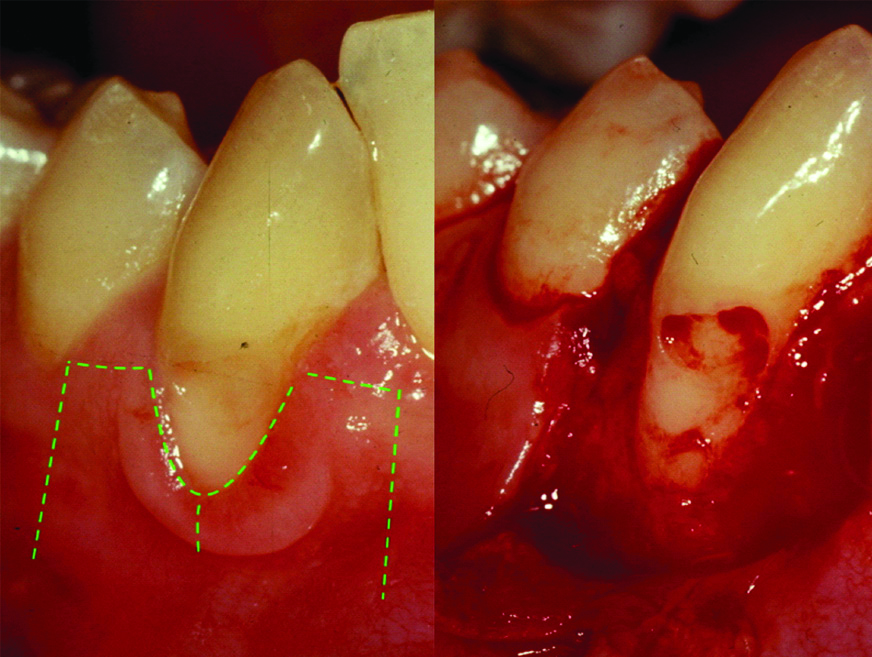

A 36-year-old female patient presented in to the periodontal clinic in 2002 with a complaint of long teeth and sensitivity in the lower right (#43) and left (#33) canines. The dental history revealed that the patient had a history of using an aggressive brushing technique, which caused generalised abrasion of the cervical region and resulted in the placement of a composite restoration to fill the abrasion area. Subsequently, gingival recession occurred in some areas, and root sensitivity reoccurred because of a leakage of these restorations. Clinical examination revealed the presence of gingival recessions of approximately 3-4 mm on teeth #33 and #43, with the presence of a composite restoration on the root surface [Table/Fig-1]. The recession defect was classified as Miller’s Class II, with 1 mm of a keratinised gingiva and no attached gingiva [1]. The probing depth ranged from 1 to 2 mm. The plaque index was 75%, with bleeding on probing of 55%. Phase I therapy consisted of scaling and root planing, with plaque control measures using a modified Stillman’s brushing technique and interdental flossing at home. The surgical phase consisted of removal of the old restoration and replaced with a new restoration which; was contoured to the crown only then, placement of a connective tissue graft, combined with a double-papilla flap. The patient agreed to the procedure and signed informed consent. Prior to soft tissue grafting, the composite restoration was removed from the root surface and contoured to the tooth crown only, and the root surface was smoothed with a finishing bur [Table/Fig-2]. The right side of the palate was used as a donor site, which was anaesthetised with one ampoule of lidocaine, while each recipient site received two ampoules. Blade #15 was used for incision placement and palatal tissue harvesting. Two oblique incisions of 3 mm long were placed on each side of the tooth, with two vertical incisions extended beyond the mucogingival junction. A partial thickness flap was utilised all the way long [Table/Fig-3]. A connective tissue graft of 13×5 mm, with 2-mm thickness after removal of adipose tissue, was harvested from the palate, and the donor site was secured with a 4-0 vicryl suture [Table/Fig-4]. The graft was divided in half, for teeth #33 and #43, respectively. The graft was then, sutured in place with a 5-0 vicryl suture using a simple interrupted technique; then, a double-papilla rotational flap was secured with 5-0 vicryl [Table/Fig-5]. No periodontal dressing was used. Postsurgical medication consisted of ibuprofen 400 mg/qid for four to seven days and rinsing with normal saline twice daily for seven days. The patient was instructed to eat soft food for seven days. Brushing of the surgical site was deferred for six weeks, and the patient was asked to use a cotton tip with mouthwash to clean the area twice daily. The sutures were removed after two weeks, and the healing was uneventful, with no complications [Table/Fig-6]. Since the patient had mild localised periodontitis, with a history of an aggressive brushing technique, she was placed on a maintenance recall every four months for suppurative periodontal therapy.

Pre-operative images for teeth #43 and #33 in 2002.

Image after composite removal from teeth #43 and #33 and root surface smoothening.

Flap design for a double-papilla flap.